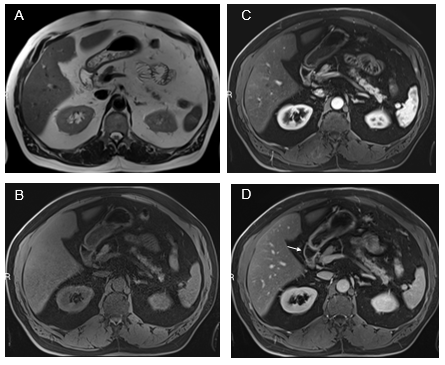

Stomach: The antral region of the stomach is the gastric portion that most commonly shows findings of inflammation (Figure 2). Increased enhancement in the arterial and venous phases is not uncommon. In the gastric portion, submucosal sparing or edema is commonly observed as a thin strip that lacks enhancement. Diffuse gastric enhancement can also be appreciated. Usually, this confers a more serious inflammatory condition of the stomach, such as moderately severe disease.

Figure 2 Axial T1-weighted GRE images. In-phase (A) and out-of-phase (B), show minimal signal drop of the liver on out-of-phase images consistent with mild steatosis. Increased mural enhancement of the stomach is better perceived in the arterial phase images (C).

Duodenum: Inflammation restricted to the first and second portions of the duodenum is the most frequent pattern (Figure 3). Attention must be paid to the gallbladder wall, as sympathetic inflammation of the adjacent gallbladder wall is not uncommon in moderate severity of disease. Also, inflammation of the ampullary region not uncommonly causes dilation of the CBD and pancreatic duct, with increased mural enhancement. Acute acalculous cholecystitis and biliary duct dyskinesia, we now consider the secondary processes of prominent duodenal inflammation, and management of these biliary abnormalities should start with treating duodenal inflammation. Full involvement of the duodenum does occur, and the severity of inflammation is usually at least moderate when the entire duodenum is involved. Inflammatory enhancement is not uncommonly observed on both arterial and venous phase images.

Figure 3 Fatty liver with simultaneous upper GI inflammation. Axial T2-weighted images (A). Axial T1-weighted GRE images pre-contrast (B) and acquired in the arterial phase (C) and the interstitial phase (D). Increased mural enhancement of the stomach, duodenum and jejunum is observed, and more conspicuous in the interstitial phase (arrows, D).